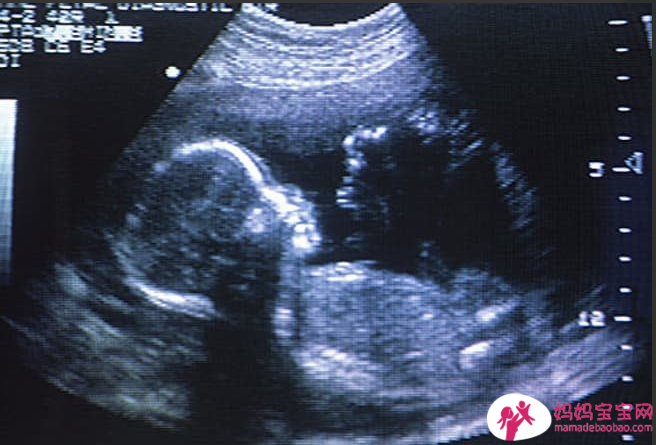

体外受精 (IVF)

当其他不孕症治疗无效时,此选项提供了希望。它在实验室中直接结合卵子和精子。然后,医生将正在生长的胚胎放入您的子宫中。试管婴儿可能很昂贵,平均周期成本为 12,000 美元至 17,000 美元,不包括药物。 2018 年,每个 IVF 周期的怀孕率从 35 岁以下女性的 50% 到 35 至 37 岁女性的约 37% 不等。随着年龄的增长,怀孕率下降。